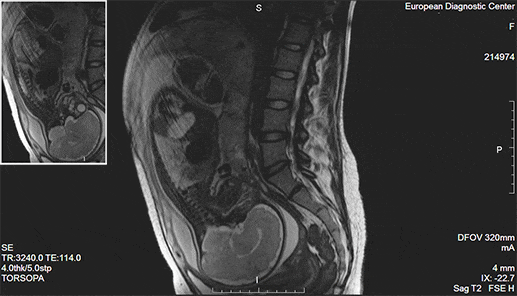

Магнитно-резонансная томография (МРТ)

Магнитно-резонансная томография появилась почти одновременно с компьютерной: в 70-х годах 20 века. Как и КТ, МРТ отображает четкие срезы нужных органов в разных плоскостях в виде контрастных черно-белых картинок и делает возможным получение 3D модели органов. По информативности и точности магнитно-резонансная томография не уступает (и где-то даже превосходит) КТ. По безопасности метод затмевает рентгенодиагностику, так как «не облучает пациентов».

Томограф представляет собой большой магнит определенной мощности. Изображения органов и тканей он строит, оценивая скорость их реакции на электромагнитные волны, которые он излучает. Чаще всего в клинической практике встречаются 1.5 Тл томографы, в большинстве случаев они дают исчерпывающую информацию о структуре тканей и органов. Показания к МРТ обширны. Это и заболевания внутренних органов, и сосудистые нарушения, и опухоли. Но явные преимущества магнитно-резонансная томография имеет при изучении патологий суставов, диагностике заболеваний головного мозга, спинного мозга, органов малого таза.

МРТ определенно перехватил бы пальму первенства у КТ и рентгена, если бы не одно серьезное «но» – исследование проводится в закрытом пространстве и длится больше часа. По этой причине оно не подойдет тяжелым пациентам, людям с клаустрофобией и психическими расстройствами. Процедуру нельзя проводить и тем, у кого есть электронные и металлические конструкции в теле, – электромагнитные волны могут нарушить их работу и положение.